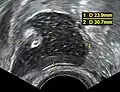

Dermoid cyst in vaginal ultrasonography -

A complex cyst due to a dermoid as seen on ultrasound -